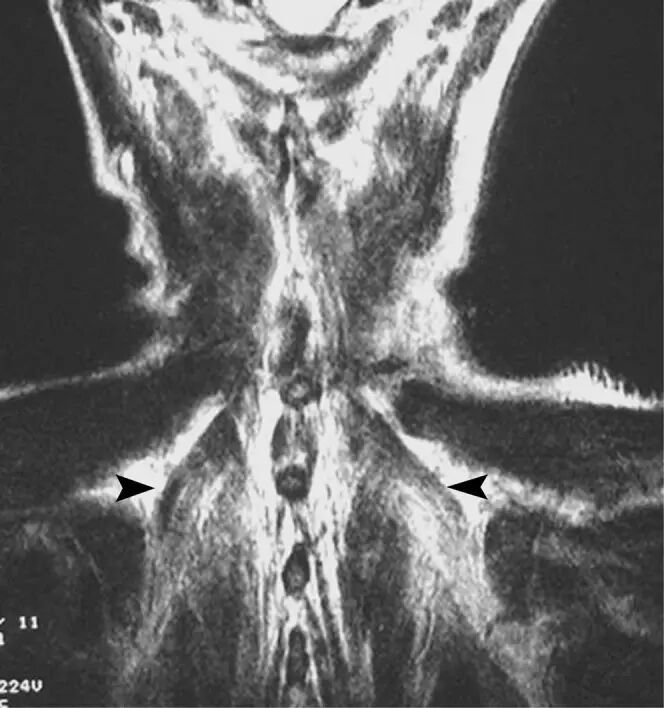

![]()

图12.一名53岁的女性,在放射治疗肺癌后出现肌肉水肿。 冠状T2加权磁共振图像显示在辐射场中的水肿和扩大的椎旁肌(箭头)。